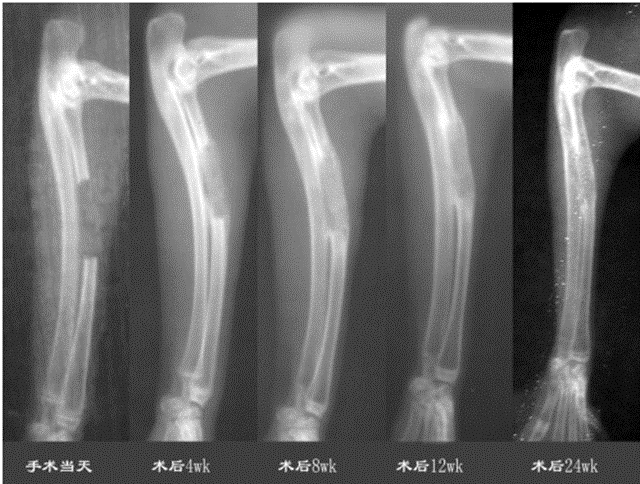

清華大學熊卓和第四軍醫大學利用PLLA/TCP復合材料,PLLATCP的質量比為7:3,制造支架的開放孔隙的孔隙率為80%,大孔孔徑約為500 μm,微孔孔徑約為5 μm。支架的外形為直徑5mm、長15mm的圓柱形;生長因子為rhBMP-2。結果顯示術后4周,骨缺損區有不均勻的低密度骨痂顯影;術后8周,骨痂顯影密度增高,骨痂外層形成皮質骨輪廓,與缺損斷端連接;術后12周,骨痂密度進一步增高,中心區出現與植入支架輪廓一致的高密度區,周圍皮質骨輪廓清晰,與斷端連接良好;術后24周,骨痂塑型完好,骨痂皮質骨與缺損兩斷端的皮質骨完全融合成一體,骨痂中心區密度降低。